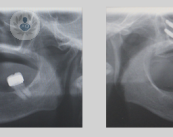

La cirugía del mentón, conocida más comúnmente como mentoplastia, es un tipo de intervención quirúrgica que, tal y como explica el Dr. Mareque Bueno, consiste en aumentar, disminuir o remodelar el tamaño vertical u horizontal del mentón.